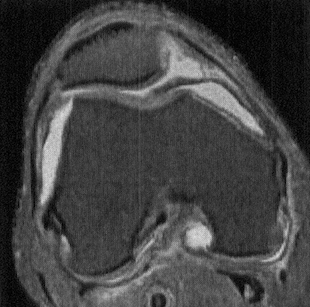

Axial PDWI FS MR shows a thick, irregular, and undulating medial parapatellar plica extending deep into the trochlear notch, and interposed between the medial trochlea and patella. Such plicae can become inflamed and thickened due to repetitive trauma during knee motion, setting up a vicious cycle of trauma and inflammation. (Andrew Sonin, StatDx, retrieved August 24th, 2015)